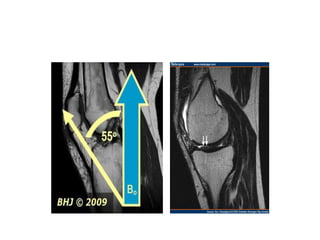

Magic angle  Tendonsand ligaments have a very short T2 relaxation time.  But, when they are oriented in 55o to the z axis their signal may increase and mimic pathology.  Appear  as a bright signal